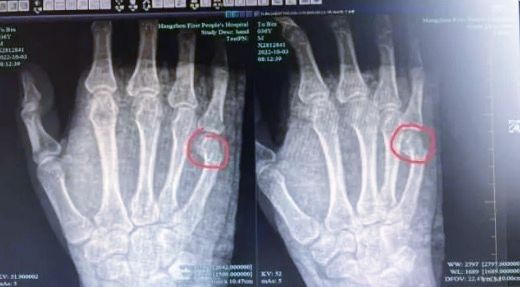

10月12日,一则与家庭教育相关的新闻登上热搜。据澎湃新闻报道,近日,杭州36岁的吴先生辅导上小学的儿子写作业时,因为一道题来来回回讲了半小时,儿子仍不理解,一气之下用手怒捶桌子,结果导致自身手掌骨折。医院检查显示:吴先生右手第5掌骨远端骨折,断端移位明显,需住院治疗。